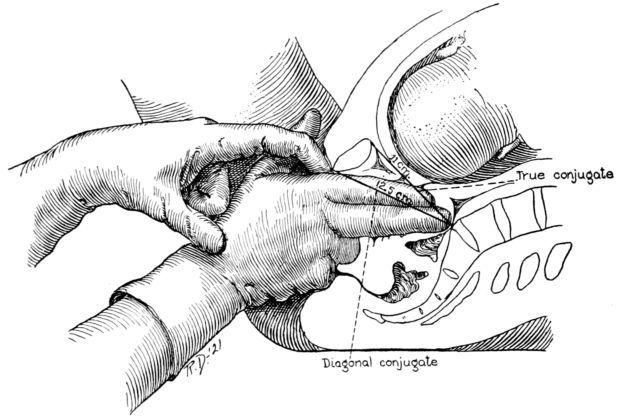

| 8. | Diagram showing method of estimating true conjugate | 28 |

The length of the all important, true conjugate is estimated by introducing the first two fingers of one hand into the vagina until the tip of the second finger touches the promontory of the sacrum. (Fig. 8.) The point at which the inner margin of the symphysis then rests upon the forefinger is measured, thus giving the length of the diagonal conjugate. This normally measures 12.5 centimetres or more, and is estimated as being 1.5 centimetres longer than the true conjugate.